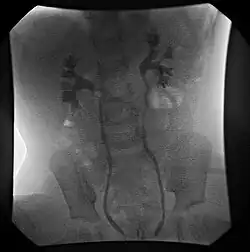

- Fluoroscopic voiding cystourethrogram (VCUG)

An abdominal ultrasound might suggest the presence of VUR if ureteral dilatation is present; however, in many circumstances of VUR of low to moderate, even high severity, the sonogram may be completely normal, thus providing insufficient utility as a single diagnostic test in the evaluation of children suspected of having VUR, such as those presenting with prenatal hydronephrosis or urinary tract infection (UTI).[4]

VCUG is the method of choice for grading and initial workup, while RNC is preferred for subsequent evaluations as there is less exposure to radiation. A high index of suspicion should be attached to any case where a child presents with a urinary tract infection, and anatomical causes should be excluded. A VCUG and abdominal ultrasound should be performed in these cases